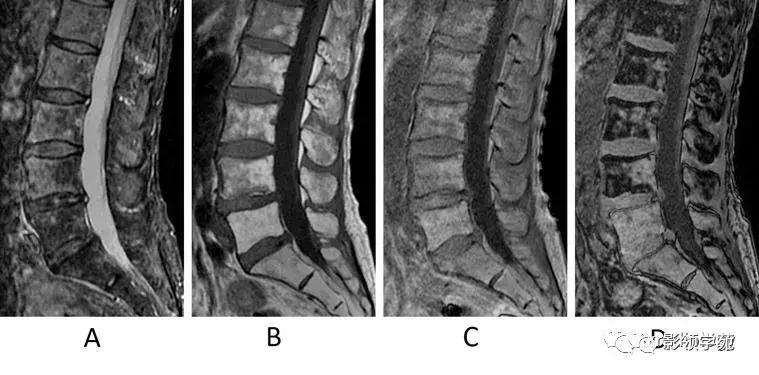

图3:椎间骨软骨病的典型病例(Modic 1型和2型)。男,50岁。

A:STIR矢状位图像,

B:T1WI矢状位图像,

C:T2WI矢状位图像,

D:STIR矢状位图像,

E:T1WI矢状位图像,

F:T2WI矢状位图像。

A-C:初次检查。D-F:18个月后复查。

最初的检查(A-C)STIR上示终板的高信号并椎间隙变窄(A箭)。该区域在T1WI上呈低信号(B箭),在T2WI上呈高信号(C箭),表明Modic 1型终板变化。

18个月后复查(D-F),发现骨髓脂肪变性,表明转变为Modic 2型改变(D,E,F箭)。部分保留的骨髓水肿在 STIR上呈高信号(D箭头)。